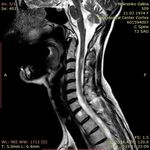

МРТ